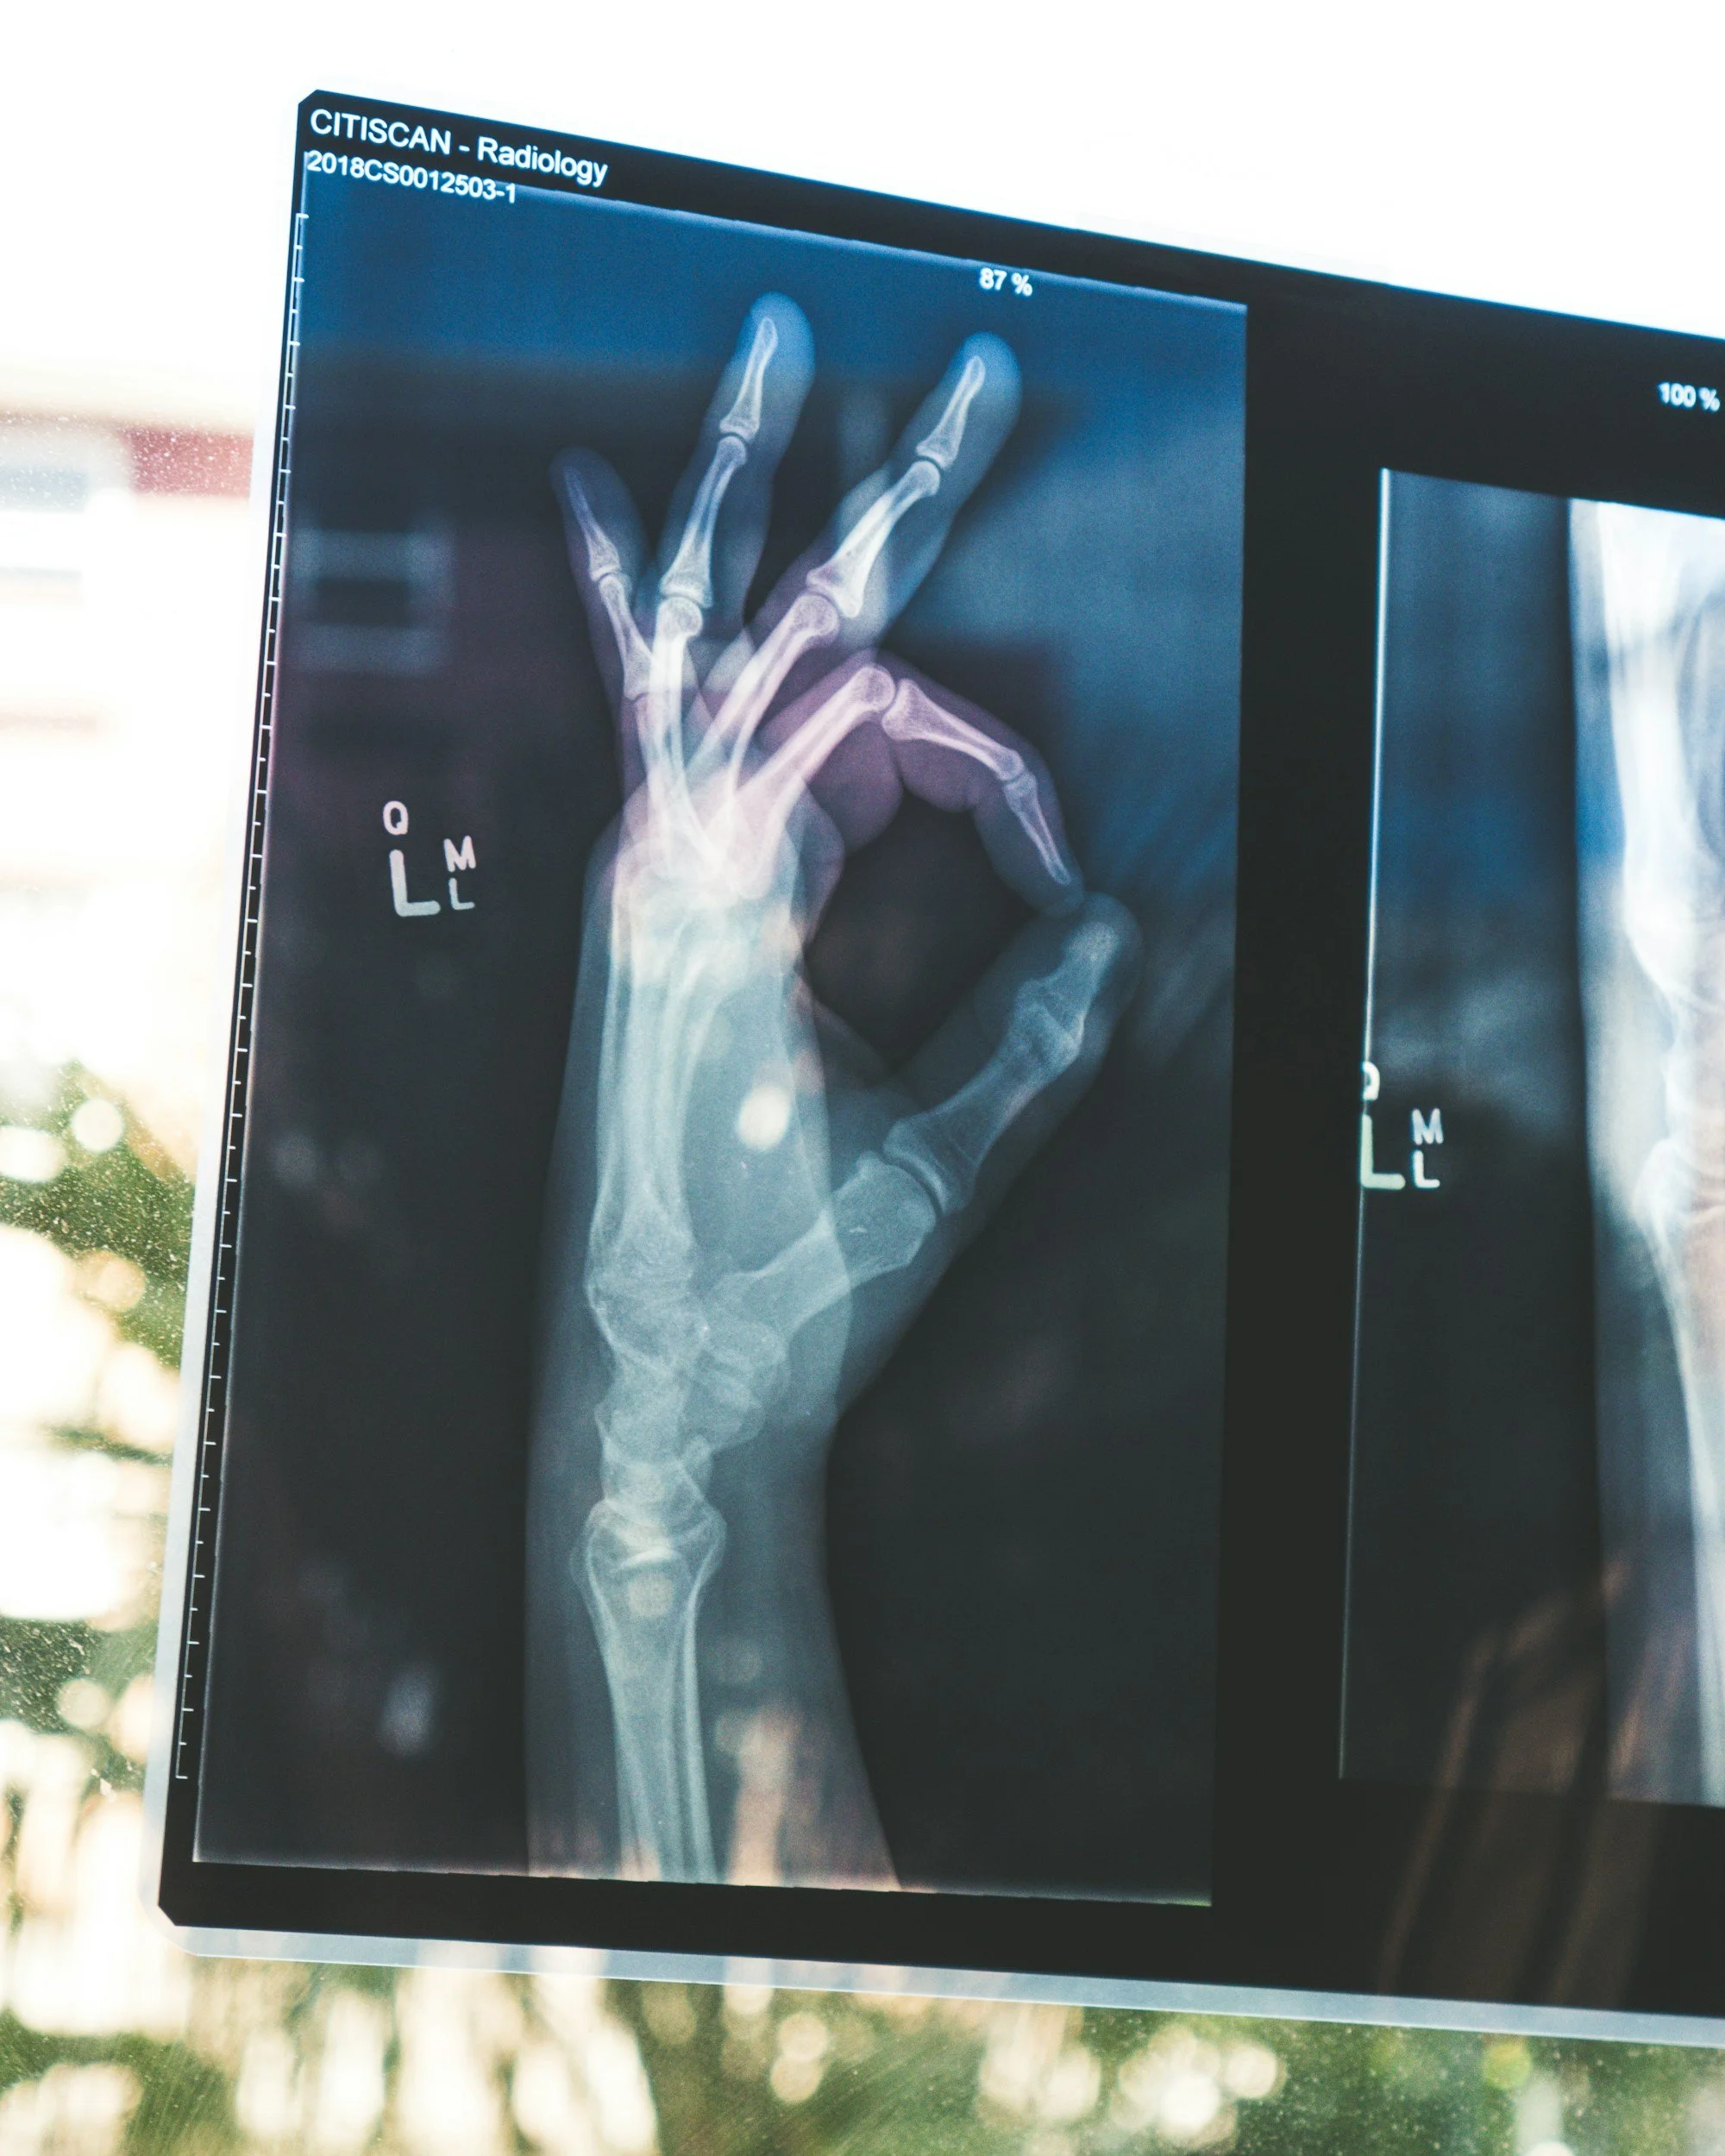

X-ray of a hand

What I noticed — again — with participants this weekend was a pattern I've seen over and over. When someone looks at an X-ray, their eyes go straight to the obvious fracture line. Which makes sense, right? That's the drama. That's the thing that screams "problem here!"

But what they're not doing is scanning the whole picture. I'm talking about angulation, rotation, alignment, joint position — the stuff that might not jump out at you but absolutely determines where that patient ends up in six weeks.

Subtle subluxation? Missed. Rotation? Not checked. Alignment on the lateral view? Glossed over.

What I want aspiring hand therapists to develop is that mental habit of properly reading an X-ray beyond the fracture line. Assess the alignment. Check the rotation. Look at the joint position. Then ask yourself: given everything I know about this bone, this fracture, and this patient — is this acceptable? And if it's not, what do I do about it now, not in three weeks when the stiffness has already set in?